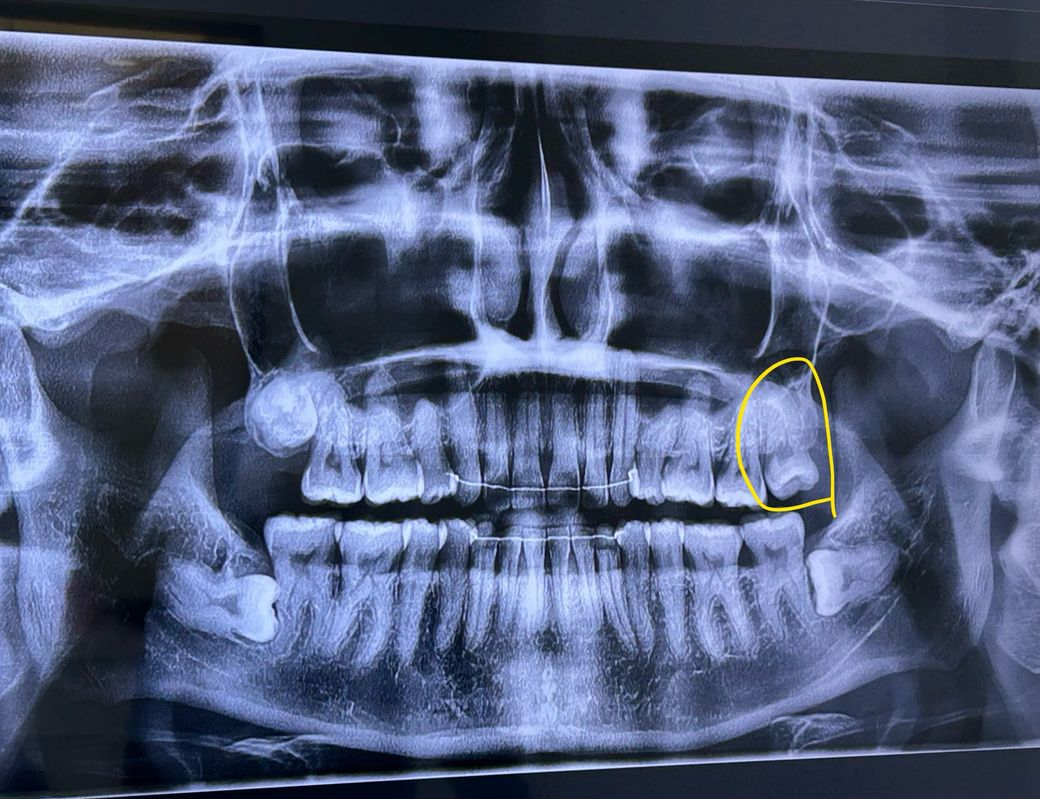

1. (노란 동그라미) 사랑니는 다 나온건지도 모르겠는데, 빼야할까요? 옆으로 삐뚤게 나긴 했는데, 충치는 없어요. 옆 어금니를 더 밀어버리거나 하는 등의 부작용이 있을까요?

2. 1번 옆 어금니가 좀 욱신 거리는데, 사랑니의 영향이 있어보이나요? (충치는 없다고 치과에서 판정)

3. 나머지 세개 어금니는 뽑아야할까요? 특히 하악 매복 사랑니는 저렇게 평생 가만이 있을수도 잇는건지, 언젠간 자꾸 밀어서 뽑아야하는지 궁금합니다.

4. 제가 상악 발치 교정을 햇는데요. 상악이 요새 다 약해진 느낌이 들어요. 상악 치아 전체 이상없는지 , 그리고 특히 분홍색 동그라미 같은건 뿌리가 휘어버린건지 궁금합니다.

1. 맹출은 끝났습니다. 옆 어금니에 영향을 줄만한 상황은 아니나 위생관리가 어렵다면 빼는게 좋습니다

2. 나머지 매복사랑니는 그냥 두는것도 나쁘지 않은 선택일 것 같습니다.

3. 교정 시 치아의 뿌리(치근)까지 다 이동하지 않는 경우도 종종 있습니다.